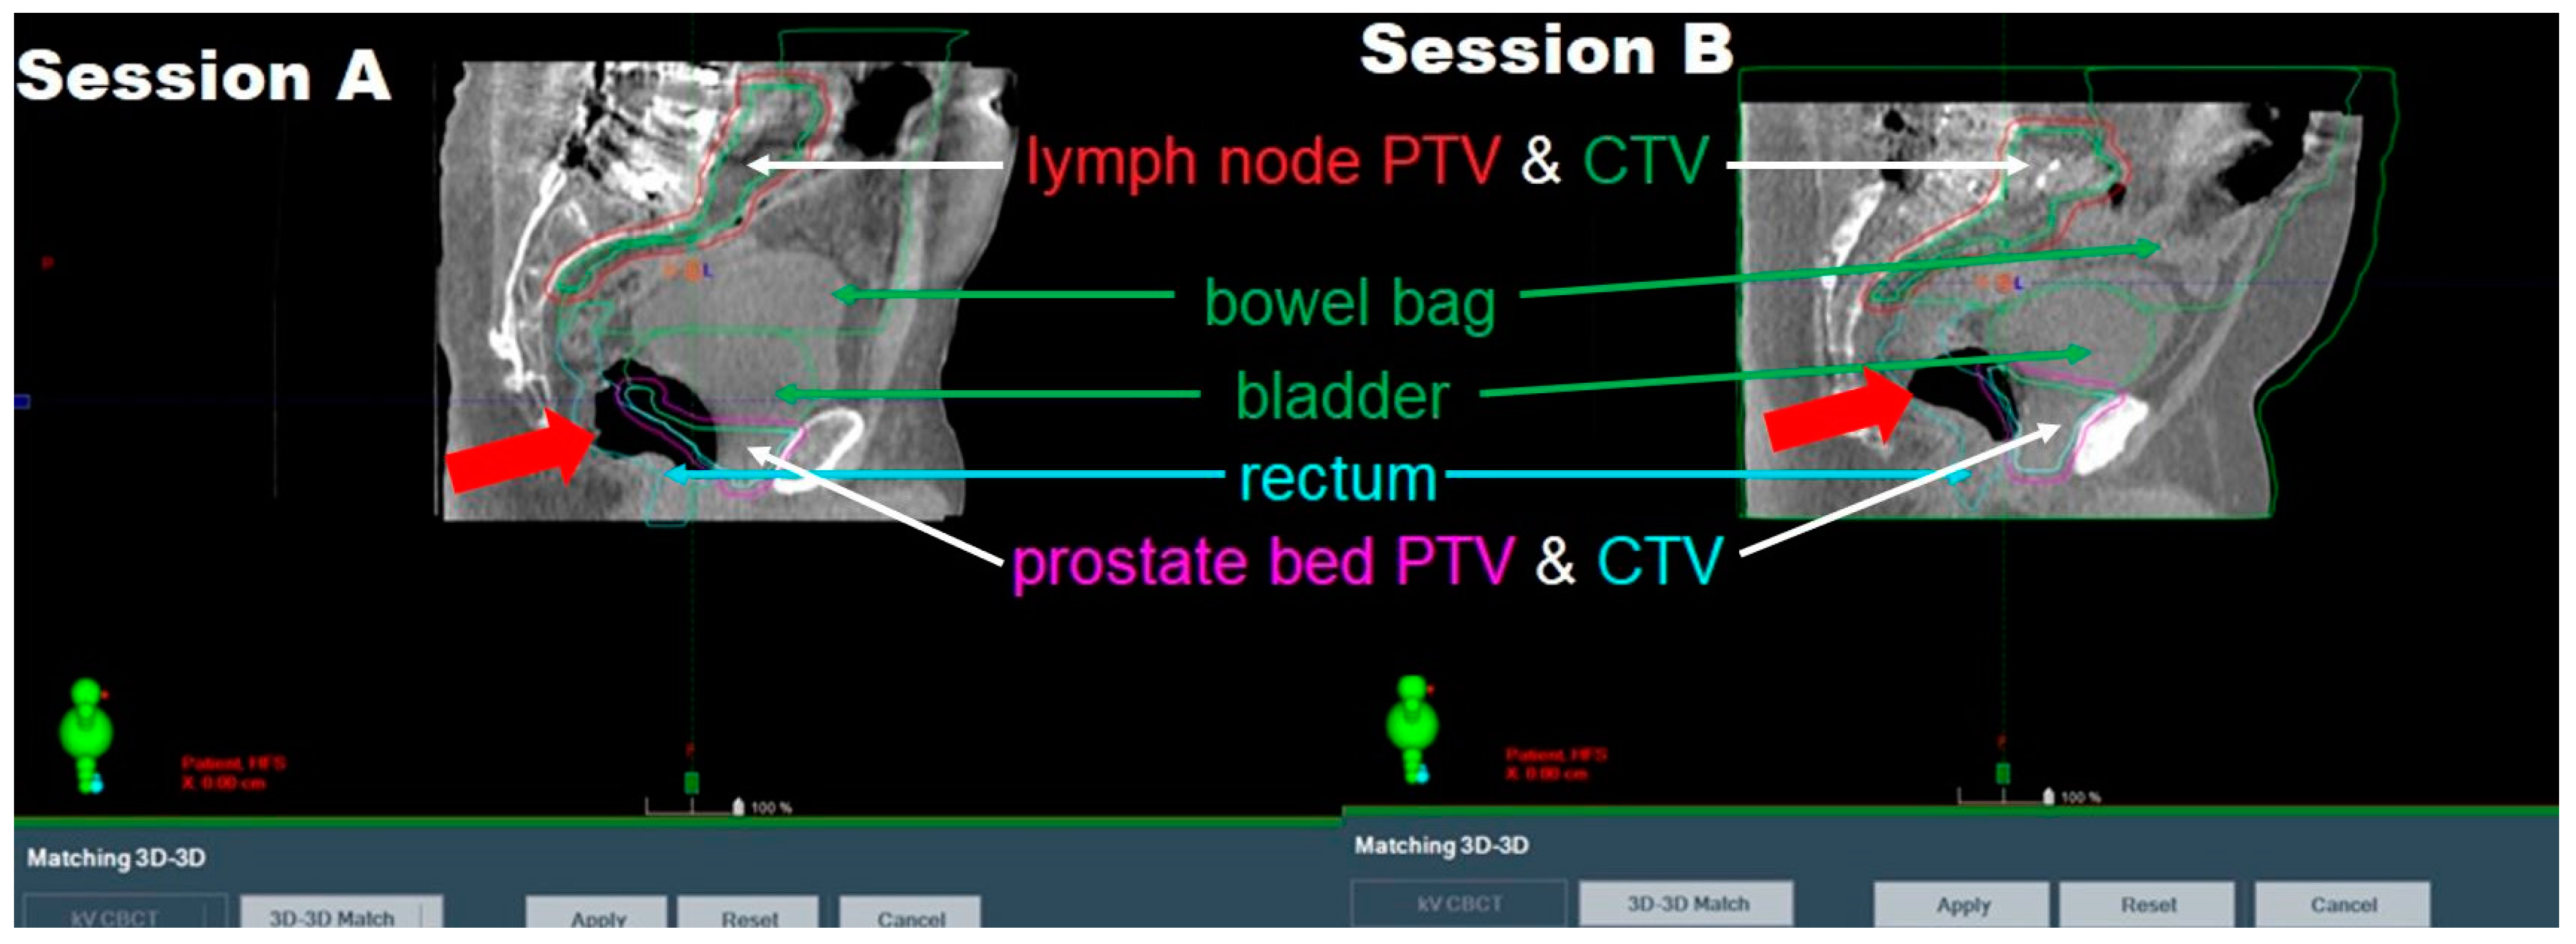

3.1. Aborted Sessions

3.2.2. Patient-Driven Challenges